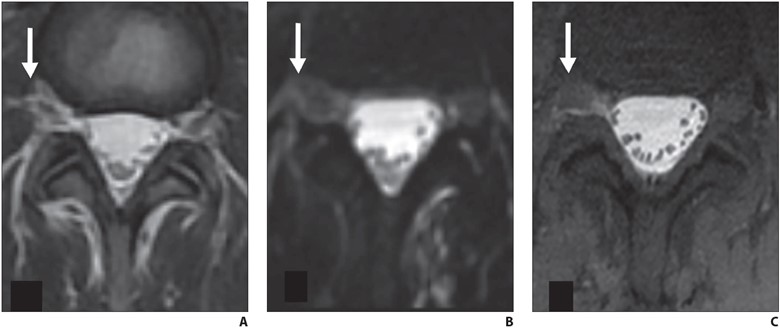

Fig. 2—Axial lumbar spine MRI findings of 39-year-old woman with orthostatic headache. (B and C adapted from [4])

A and B, Axial T2-weighted (A) and heavily T2-weighted fat-saturated (B) images do not delineate any clear extradural fluid. T2-weighted hyperintensity lateral to dura (arrow, A) blends with fat and epidural veins (A). Three-dimensional CSF leak protocol shows minimal T2-weighted asymmetry (arrow, B) in right L4–5 neural foramen at same level (B).

C, Delayed T1-weighted fat-saturated image with intrathecal gadolinium confirms extradural CSF (arrow) at this level. Patient was treated with transforaminal epidural fibrin patch that relieved symptoms.